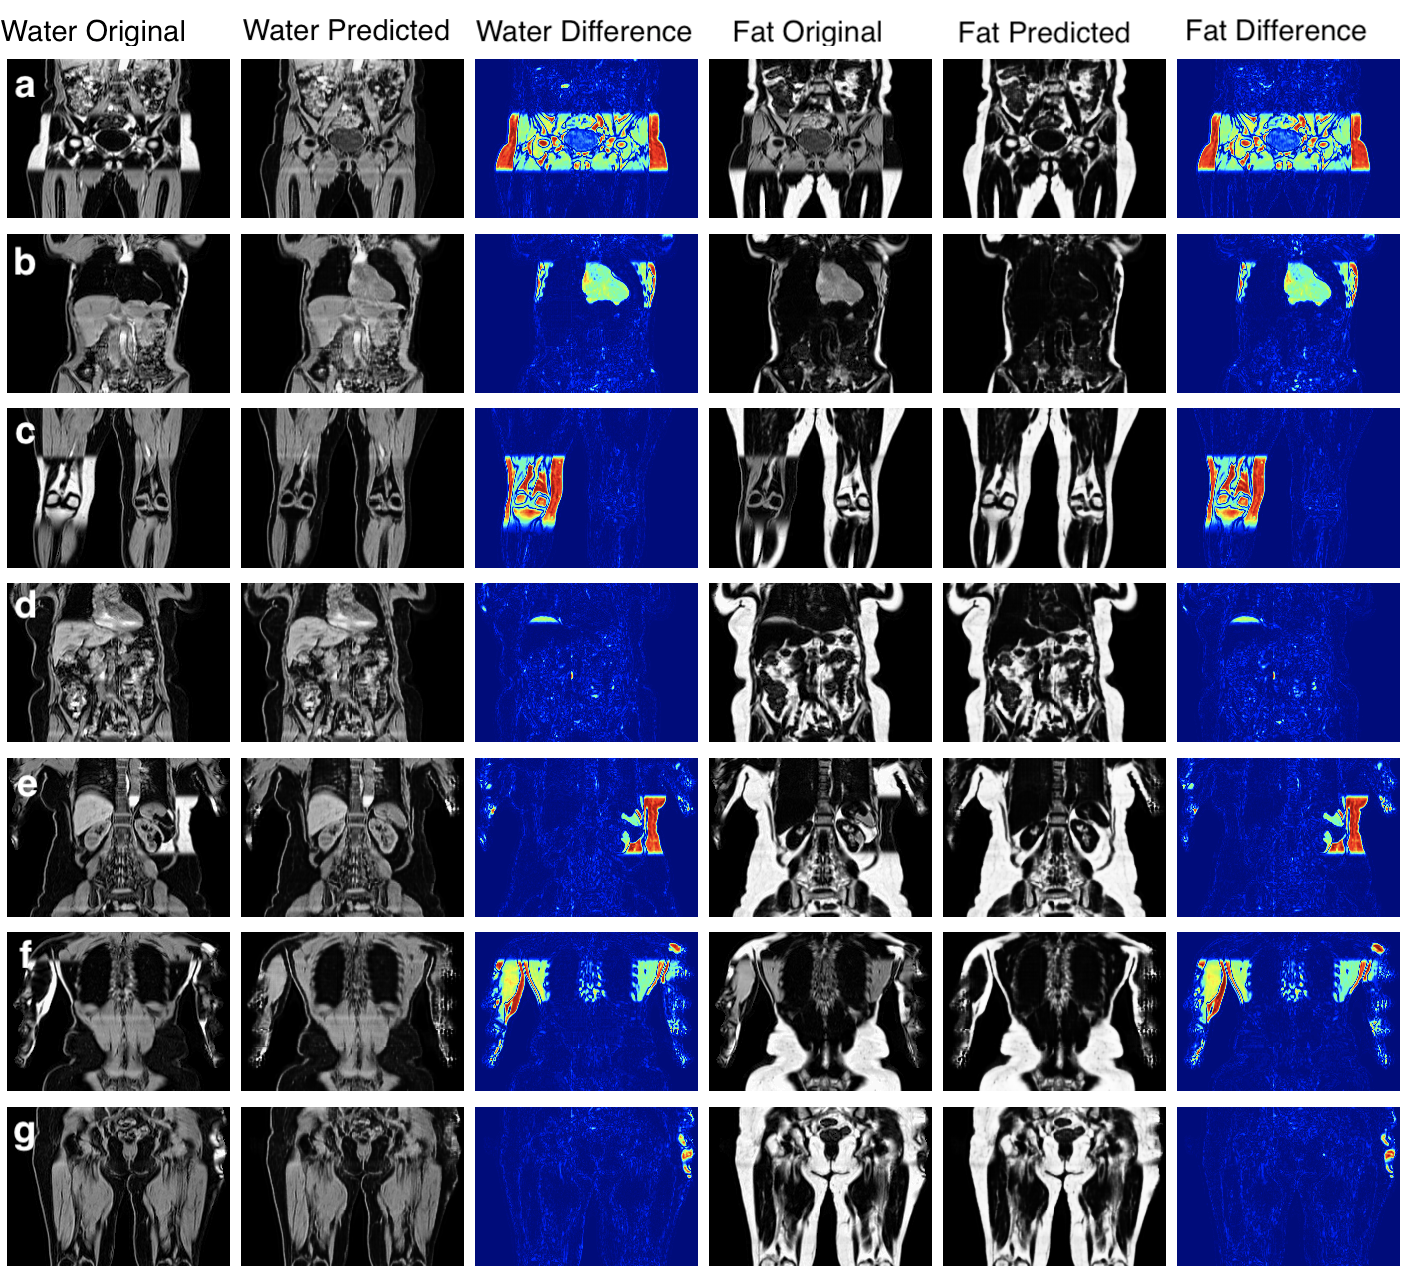

Fig. 3 shows the ground-truth data, predictions and their absolute difference for the fat and water channels of a participant in the testing set. Model predictions and the original data from the scanner for participants affected by various fat-water swaps are provided in Fig. 4. The examples were selected to illustrate the performance of our model in a variety of scenarios: data that are not affected by major swaps, data affected by swaps that cover an entire series in the acquisition (Fig. 4 a, c), as well as data displaying complex partial (Fig. 4 b, d, e) and/or boundary swaps (Fig. 4 f, g). The absolute difference images in columns 3 and 6 of Fig. 4 highlight where the original data have been affected by a fat-water swap in the scanner reconstruction but the model correctly predicted the fat and water channels. Fig. 5 provides examples of 3D segmentations using data that suffered from fat-water swaps (top row) and the segmentation when using our model predictions (bottom row) for the following organs and tissue (from left to right): abdominal subcutaneous adipose tissue, left kidney, spleen, and left/right iliopsoas muscles (red and green, respectively). The predictions shown in Figs. 3 and 4, as well as the underlying volumes used for the 3D segmentations in Fig. 5, are outputs of the final dual-input model, which performed the best across all of our experiments.

We have shown that our single- and dual-input models are able to predict swap-free fat and water volumes. Processing the entire neck-to-knee volumes, for example those found in the UK Biobank abdominal protocol, takes approximately eight seconds per scan. We have established the high quality of our results through quantitative metrics such as PSNR and SSIM (with average values consistently ) for the dual-input model in both cross-validation experiments (Table 1) and out-of-sample test data on final versions of the models (Table 2). We have shown qualitative performance on scans where the scanner software failed to adequately separate the fat and water channels during reconstruction in visual examples (Fig. 3) and by comparing to dixonfix to establish our method does not induce fat-water swaps (false positives). As a final qualitative validation we used the predicted channels as input to 3D segmentation models and have shown how the corrected data produces superior segmentations.

We successfully separated fat and water channels for 3D Dixon MRI in our three experiments, where the best model utilises both the in-phase and out-of-phase data as input with L1 loss. We have shown that our method correctly separates and channels and is able to overcome a wide variety of fat-water swaps, including those explicitly excluded from the training data (e.g., swaps that completely cover one of the series acquired, cover half the series in the legs, top-of-the-liver swaps). However, minor fat-water swaps located at the boundary of the field of view or only involving the arms were included in the training data as they occur infrequently and at random anatomical locations. We hypothesise that the infrequency and randomness of these types of swaps in the training data means that the model ignores them when optimising the generator. In Fig. 4, particularly rows e-g, it appears that the model is able to ignore and minimise the effect of the those swaps even though they were almost certainly present in the training data.